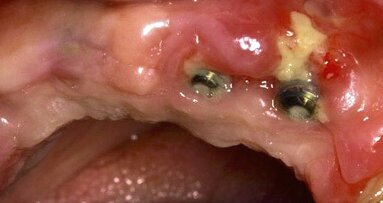

“Según la Encuesta Nacional de Salud y Nutrición de Medio Camino 2016, el 86% de los mexicanos reciben atención bucal a través del Sistema Nacional de Salud y las dependencias que lo integran. El número de odontólogos que laboran en instituciones públicas se ha incrementado de manera muy importante en los últimos años, aumentando también el número de consultas anuales que se otorgan a la población. Sin embargo, a pesar de los grandes esfuerzos por abatir los índices de prevalencia e incidencia de las principales enfermedades de la boca, no se han logrado reducciones contundentes a las cifras de prevalencia de caries, enfermedades periodontales, maloclusiones, traumatismos dentales o cáncer bucal. De acuerdo a los datos reportados por el Sistema de Vigilancia Epidemiológica de Patología Bucal (SIVEPAB), la caries sigue siendo un problema de salud pública en nuestro país, afectando a todos los grupos de edad. Es muy importante educar a la población, modificar las leyes para que todos los niños adopten buenos hábitos de higiene bucal y nutrición desde la etapa escolar, y así lograr nuevas generaciones de mexicanos sanos. Es imperativo empoderar al paciente para que se responsabilice de sus factores de riesgo y evitar que enferme; también lo es formar recursos humanos odontológicos con una fuerte carga curricular en prevención y mantenimiento de los pacientes sanos”